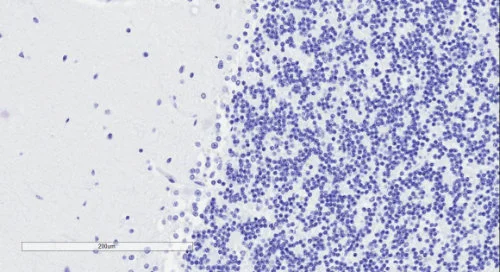

| EB11147 | Goat Anti-SYNGAP1 (aa1169-1183) Antibody | Pep-ELISA, WB, IHC, IF | Human, Mouse, Rat, Dog, Pig, Cow | 100µg/200µl |